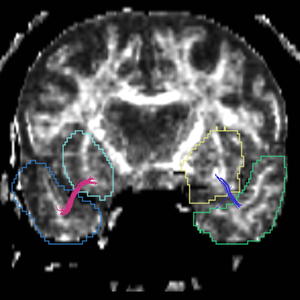

Region

caseD00917

caseD00920

caseD00924

caseD00928

caseD00935

caseD00936

caseD00938

caseD00939

caseD00940

Uncinate Fasciculus

Internal Capsule

Fornix

Cingulum

Arcuate Fasciculus